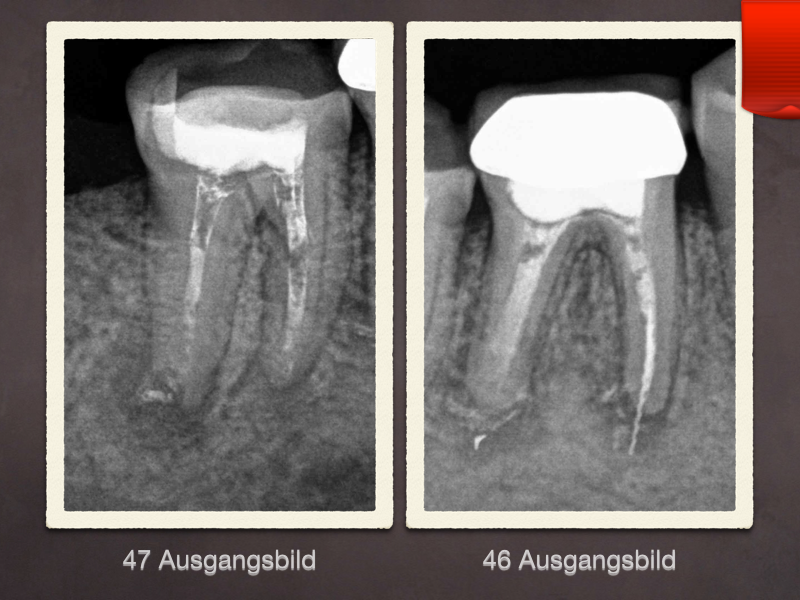

Ausgangsbild

Kollagen und MTA